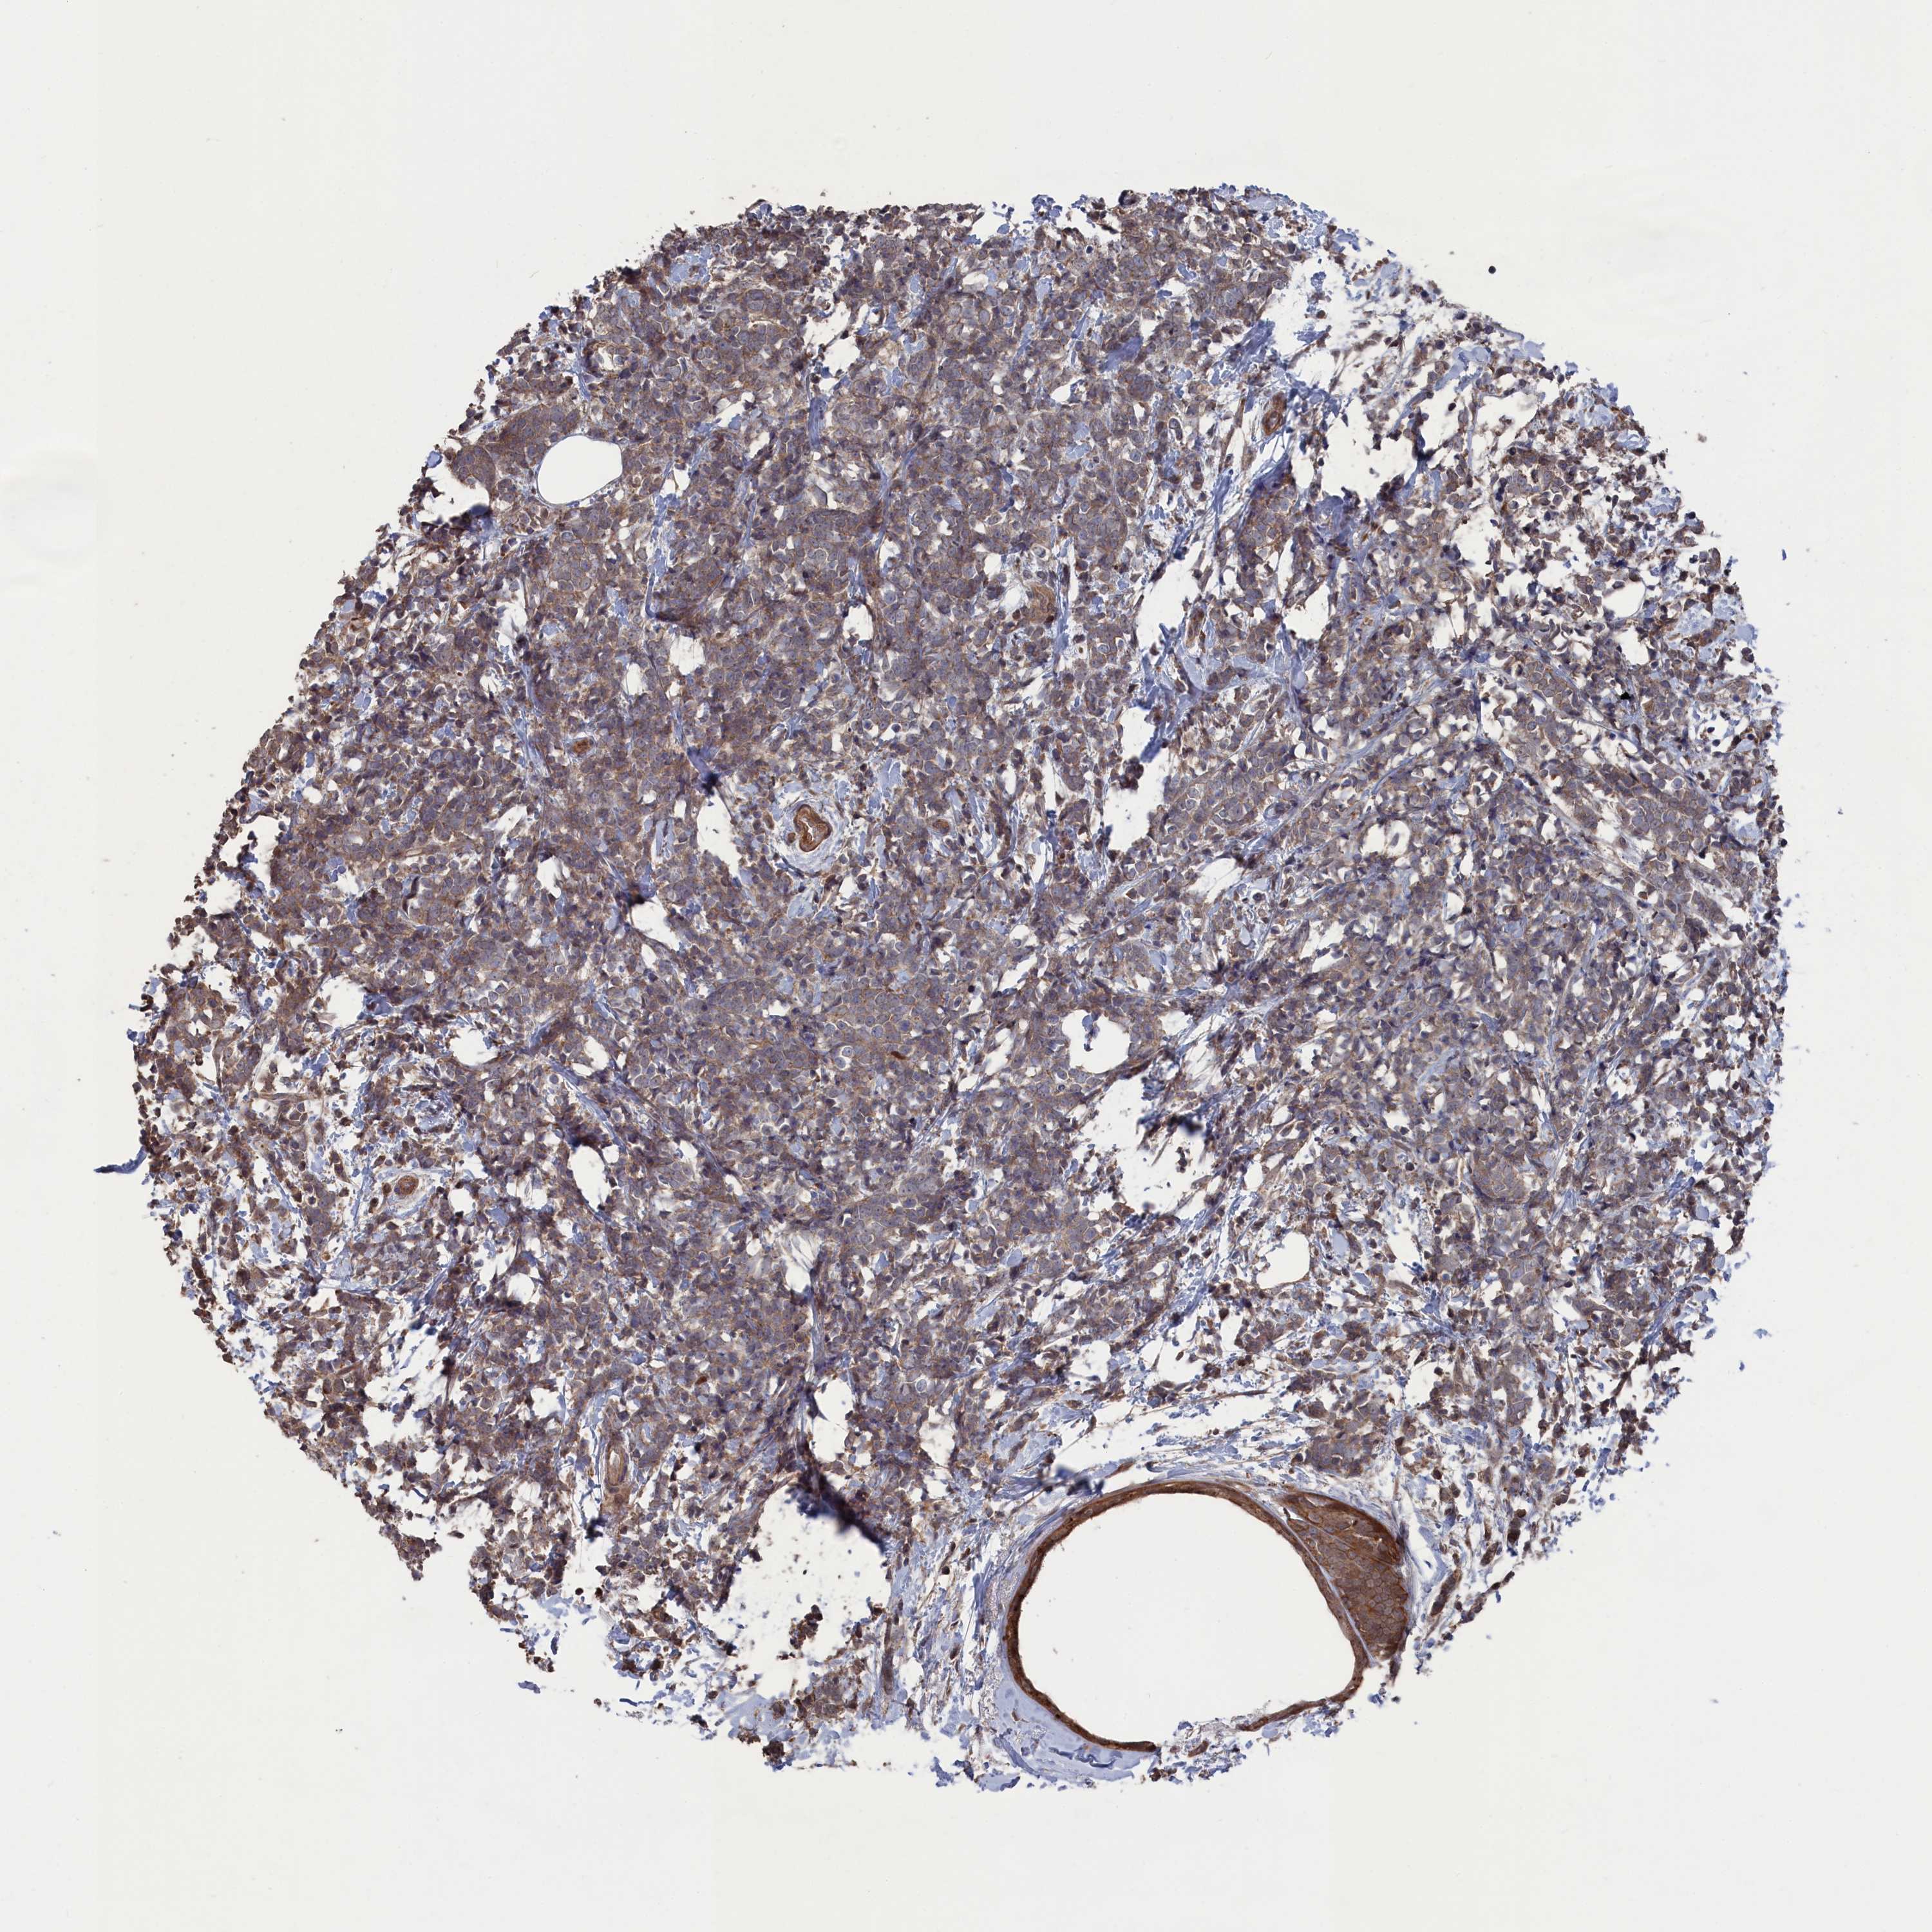

CANCER BREAST CANCER Show tissue menu

Breast cancer

Human cancer